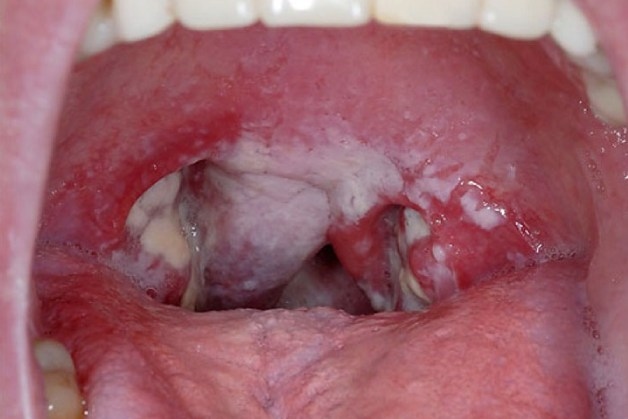

Bệnh bạch hầu là nhiễm trùng, nhiễm độc cấp tính nặng có nguy cơ tử vong cao. Bệnh lây truyền chủ yếu qua đường hô hấp, gây tổn thương ở vùng vòm hầu, họng, thanh quản, mũi, đôi khi ở da và vùng niêm mạc khác. Vì thế mà không ai được chủ quan về bệnh truyền nhiễm này.